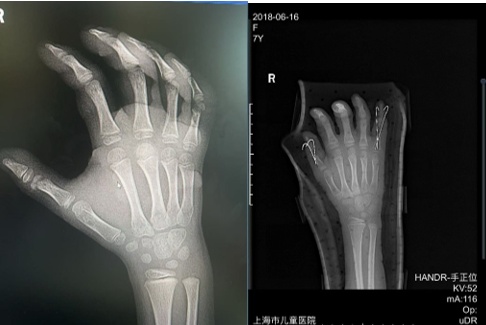

(图1)来我院时手部肿胀明显

(图3)术后一周肿胀已明显消退

(图4)二期行指骨骨折复位内固定术

(图5)目前手指感觉正常,血运良好。